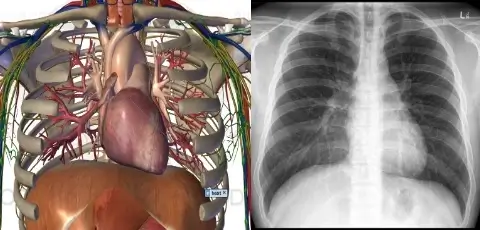

The teaching of anatomy to maritime medics is integrated with other clinical procedures. Bone anatomy is taught alongside a demonstration of a skeleton and X-rays of fractures.

Neck anatomy is covered in parallel with Doppler ultrasound of the major vessels and practice in intubation. Chest anatomy is taught alongside X-rays showing pneumothorax, pneumonia, and pleuritis. The anatomy of the liver, pancreas, spleen, and major abdominal vessels is demonstrated using artificial models and ultrasound examination on volunteers.

Every commercial vessel that travels long distances away from ports must be equipped with an X-ray machine. Maritime medics need to have basic knowledge of radiology, starting with a list of kV and mAs values to be used in each case. They should have a fundamental understanding of the images they produce, ensuring that the final result sent to the central station for diagnosis is usable. Additionally, internet connection with the central station is not always guaranteed. As mentioned, radiology is taught alongside anatomy.